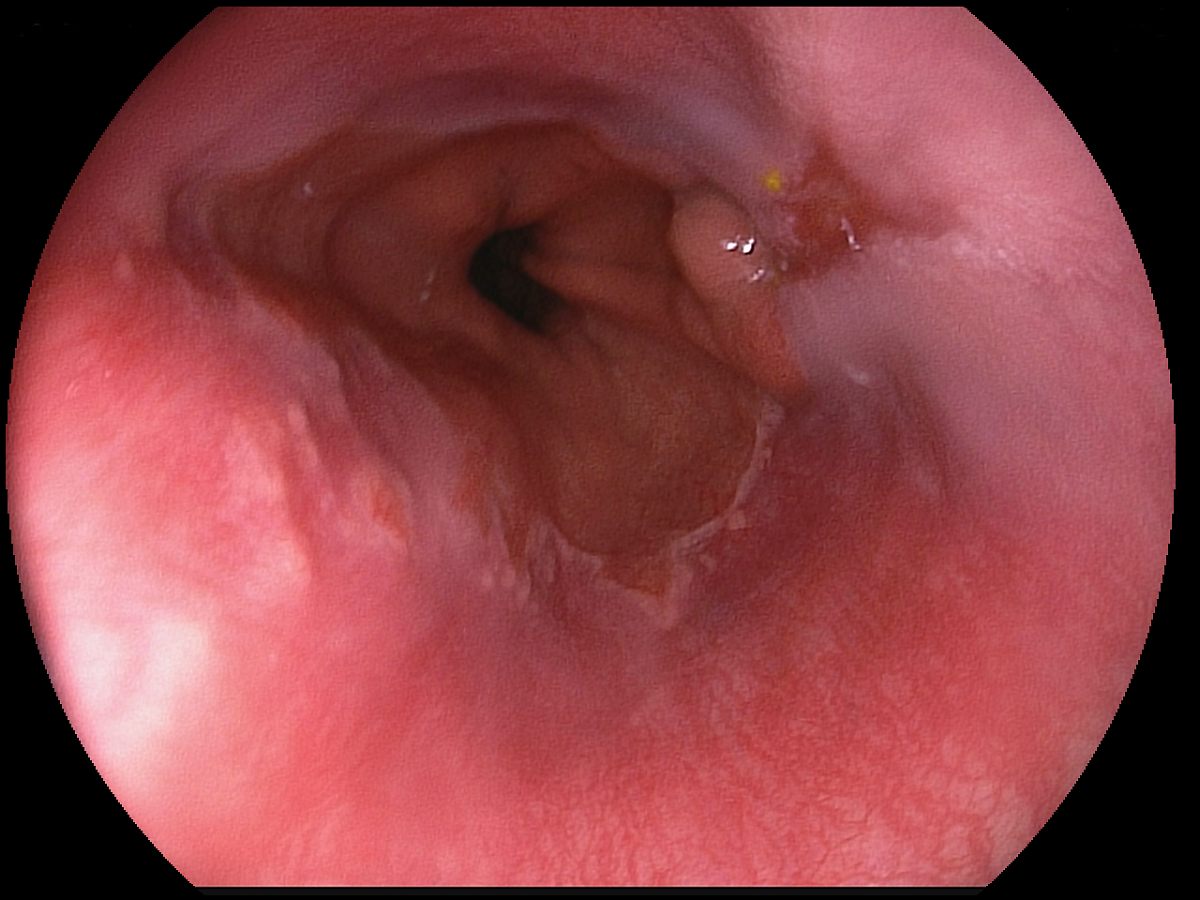

Reflux oesophagitis grade C-D according to the Los Angeles classification